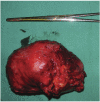

Solitary fibrous tumor (SFT) is a rare mesenchymal neoplasm which may be found everywhere in the body. It is now distinguished into two forms, pleural and extrapleural, which morphologically resemble each other. Abdominal localizations are quite rare, with 10 cases only reported in bladder; rarely they can be source of paraneoplastic syndromes (i.e., hypoglycemia secondary to insulin-like growth factor). In April 2006 a 74-year-old white male presented with chills, diaphoresis and acute abdominal pain with hematuria. At admission in emergency he underwent an abdominal Xray (no pathological findings) and an ultrasound examination of the kidneys and urinary tract, which revealed a pelvic hyperechogenic neoformation measuring approximately 10×8×7 cm, compressing the bladder. Blood chemistry at admission revealed only a mild neutrophilic leucocytosis (WBC 16600, N 80%, L 11%), elevated fibrinogen and ESR, and hypoglycemia (38 mg/dL). Macro scopic hematuria was evident, while urinocolture was negative. Contrast enhanced CT scan of the abdomen and pelvic region revealed a large round neoformation dislocating the bladder, with an evident contrast-enhanced periphery and a central necrotic area. Continuous infusion of glucose 5% solution was necessary in order to maintain blood glucose levels above 50 mg/dL. The patient underwent complete surgical resection of an ovoidal mass coated by adipose tissue, with well delimited margins; histological findings were consistent with solitary fibrous tumor (SFT). Hypoglycemia resolved completely with removal of the growth. In this case report we describe a SFT growing in the bladder, a quite rare localization, which presented a unique hypoglycemia. In contrast to the majority of cases reported in the literature, the behavior of this SFT was not aggressive, and, since the patient is still alive, surgical resection was considered conclusive.